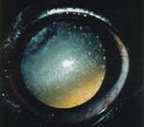

A cataract is any opacity within a lens. The opacity can be very small (incipient cataract) and not interfere with vision. It can involve more of the lens (immature cataract) and cause blurred vision. Eventually, the entire lens can become cloudy, and all functional vision lost. This is called a mature cataract. Some mature cataracts will transform over time into hyper mature cataracts.

Immature, mature, and hyper mature cataracts can cause a serious reactive inflammation inside the eye (Lens Induced uveitis, that must be medically treated, It can lead to complications such as glaucoma or a detached retina if cataract surgery is not performed, and This uveitis decreases the success rate of cataract surgery.

In dog with diabetes, cataracts develop very fast and they can lead to medical and surgical emergency. Once a lens has developed a cataract, it should removed surgically. cataract surgery is extremely delicate surgery and is performed under general anesthesia with high-magnification using an operating microscope. Some dogs require anti-inflammatory medication for several weeks, months, or lifetime following cataract surgery.